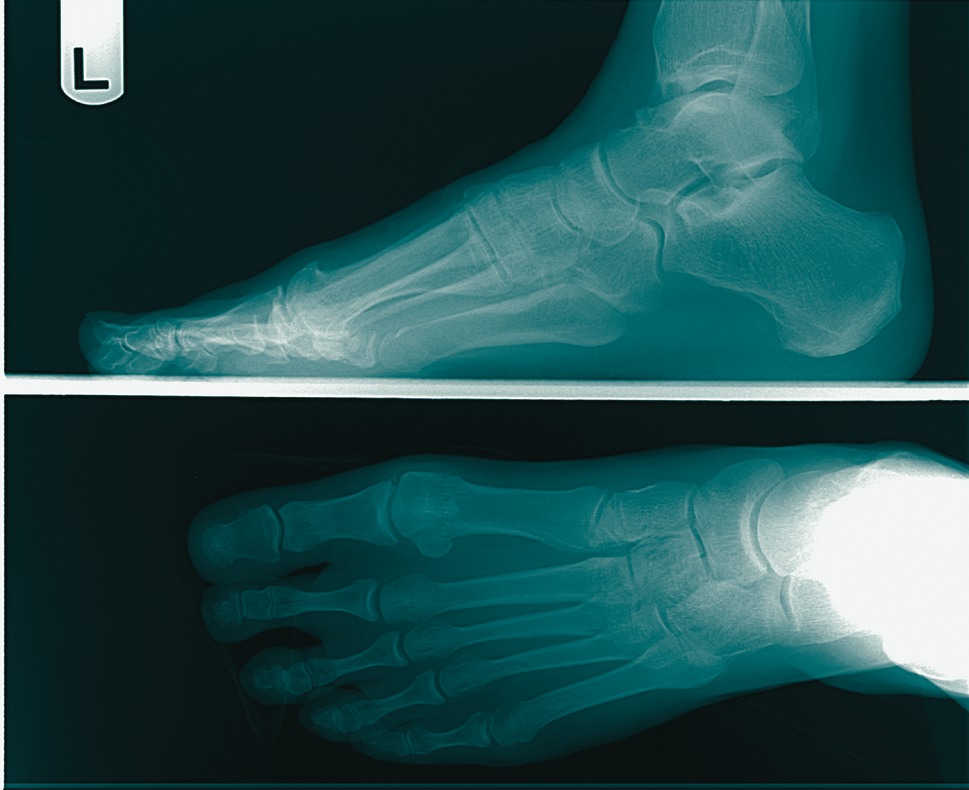

As I get more in tune with patient care, I find that the simple cases such as hallux limitus are more difficult than I initially thought because they are often more complicated and involved than the original examination might show. I have come to this conclusion after being burned by a couple of trouble cases and learning what to look for as a result. A typical patient is a 47-year-old female with chronic pain in the great toe. She has trouble in dress shoes and has mild limitation of shoegear. The patient reports having mild pain when playing golf and there is some redness of the dorsum of the foot with ambulation and activity. An examination of the region shows mild dorsal spurring and limitation of motion to 25 degrees of dorsiflexion and 20 degrees of plantar motion. She has mild dorsal pain to pressure and her end range of dorsal motion shows mild crepitus. There is no gross pain in the plantar metatarsal head and she has no medial pain and no gross stiffness or clicking of the joint. Radiographs show a very small dorsal spur. There is no gross deviation of the joint or gross arthritic changes of the joint. The patient does have mild elevatus of the first metatarsal. Although there is elevatus of the first ray on radiographs, the first ray is slightly plantar to the other rays when the patient is at rest or in a non-weightbearing position. With standing, the ray elevates due to some laxity of the first metatarsocuneiform region.